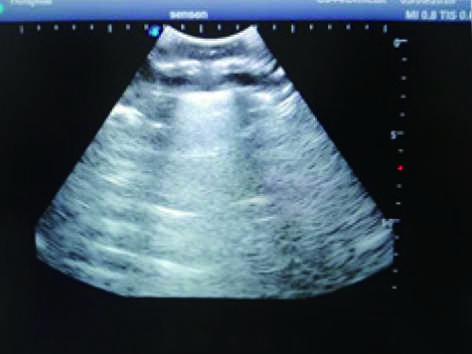

Thoracentesis Ultrasound Training Model

Model TYE1567

This model is an ideal choice for ultrasound-guided thoracentesis training with true-to-life skin feel and touch, accurate anatomical structures as well as real clinical ultrasound images. Realistic resistance to needle tips and correct landmarks provide excellent hands-on experience.

2)  Real clinical ultrasound images with clear muscles, connective tissues, lungs and pleural structures